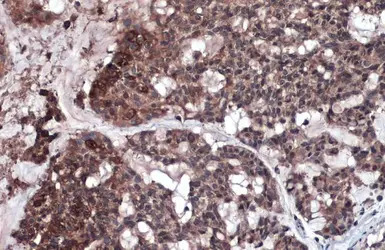

RIP3 antibody detects RIP3 protein at cytoplasm by immunohistochemical analysis.

Sample: Paraffin-embedded human breast carcinoma.

RIP3 stained by RIP3 antibody (GTX131188) diluted at 1:1000.

Antigen Retrieval: Citrate buffer, pH 6.0, 15 min